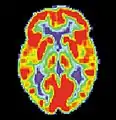

La maladie d'Alzheimer (MA) est une maladie cérébrale progressive, dégénérative et fatale, dans laquelle est recensée une perte importante des cellules. Par conséquent, la mort des cellules cérébrales survient, bien que cette maladie soit la forme de démence la plus répandue[10]. À travers le monde, il existe 1 à 5 % de la population atteinte de la maladie d'Alzheimer[11]. Il est estimé que 500 000 Canadiens souffrent actuellement de la maladie d'Alzheimer ou d'une autre démence liée. Elle est la cause de handicap la plus répandue chez les individus âgés de 65 ans ou plus[10]. Les femmes sont disproportionnellement atteintes par cette maladie[12].

Scan par TEP d'un cerveau en bonne santé.

Scan par TEP atteint de la MA.